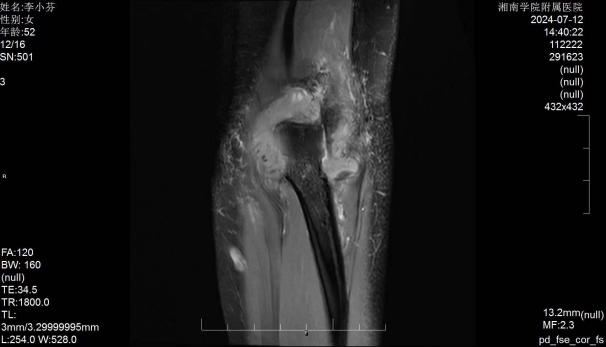

郴州市的李女士,因肘关节疼痛伴活动受限多年,辗转多家医院就诊,曾采用康复锻炼、封闭治疗、小针刀等多种方式进行治疗,均未能完全缓解。随着时间推移,李女士肘关节活动度受限逐步加重,屈、伸时疼痛,对日常生活造成很大困扰。听闻湘南学院附属医院骨二科李杨教授在关节微创治疗有丰富治疗经验,遂慕名而来。骨二科主任李杨教授经过详细的病史问询、物理查体、影像学检查,确诊李女士为左肘关节僵硬及肘关节滑膜炎性增生。住院后经过严密的术前分析讨论,最终决定采用微创技术为李女士实施关节镜下肘关节滑膜清理+关节松解术进行治疗。

术前影像学资料